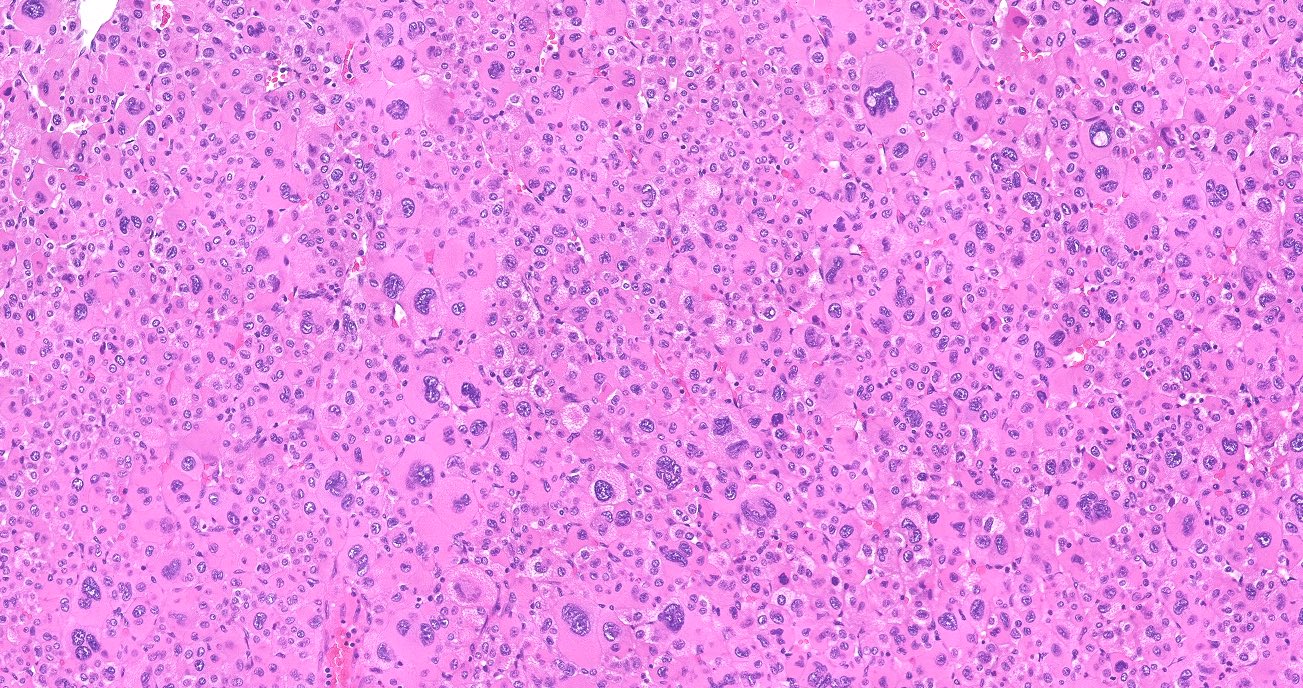

Microscopic (histologic) description

- In comparison to surrounding adrenal gland, adenoma cells are larger with different cytoplasm, increased variation in nuclear size

- Distinct cell borders, cells have abundant foamy cytoplasm reminiscent of zona fasciculata

- Balloon cells: clusters of cells with enlarged lipid-rich cytoplasm (seen in Cushing syndrome)

- Histologic variants: oncocytic, myxoid

Microscopic (histologic) images

Contributed by Xiaoyin "Sara" Jiang, M.D., Debra Zynger, M.D., @Andrew_Fltv on Twitter and @SueEPig on Twitter